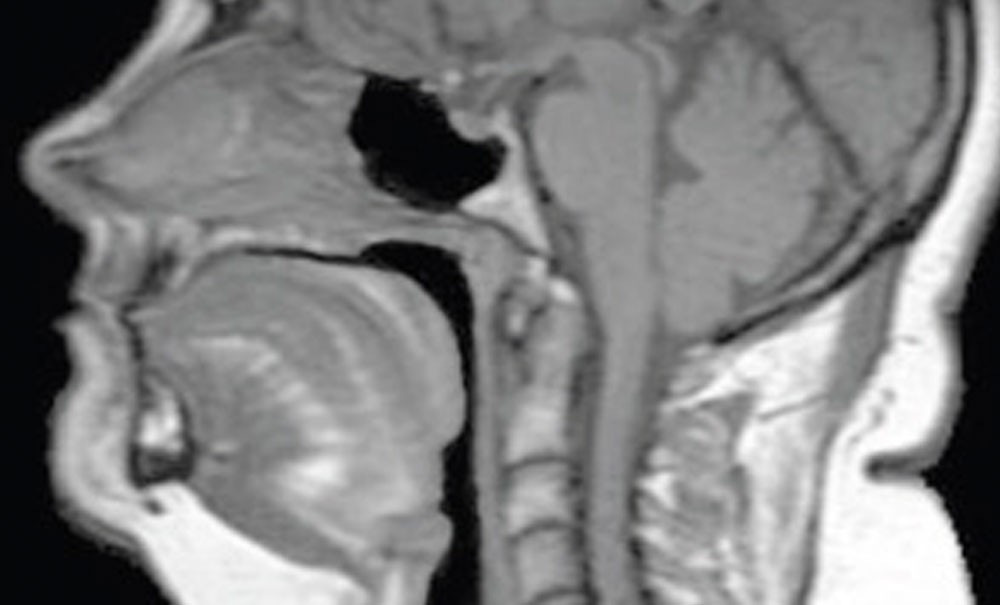

Le Syndrome d’apnées et hypopnées obstructives du sommeil (Sahos) est une pathologie chronique, fréquente dans la population générale d’âge moyen, touchant les Voies aériennes supérieures (VAS), et pour laquelle la ventilation nocturne est impactée par des fermetures intermittentes et cycliques, partielles ou totales, de ces VAS. L’enregistrement polysomnographique nocturne permet le diagnostic du Sahos, notamment en mettant en évidence ces anomalies sur l’aspect du flux nasal et sur l’existence d’efforts respiratoires augmentés. Ces apnées (cessations totales du flux nasal) et hypopnées (diminutions prolongées de l’amplitude du flux nasal) entraînent de nombreuses conséquences, dont une hypoxémie intermittente nocturne, une augmentation du stress vasculaire et une fragmentation du sommeil, tenues pour responsables des conséquences cardiovasculaires et cliniques de la pathologie.